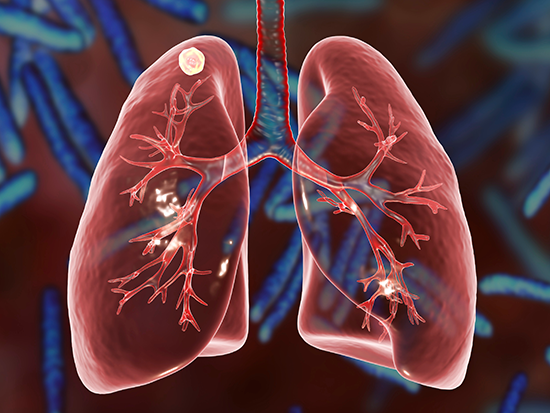

केन्द्रका निर्देशक डा। श्रीराम तिवारीले जारी गर्नुभएको विज्ञप्तिमा क्षयरोग (टीबी) विश्वभर लाखौँ मानिसलाई प्रभावित गर्ने सरुवा रोग भएको र नेपालमा यो जनस्वास्थ्य समस्याको रुपमा रहिआएको उल्लेख छ । सन् २०२३ मा विश्व स्वास्थ्य सङ्गठनका अनुसार नेपालमा अनुमानित ६८ हजार नयाँ क्षयरोग प्रभावित व्यक्तिहरू थिए, जसको दर प्रति एक लाख जनसङ्ख्यामा २२९ रहेको थियो । त्यसैगरी क्षयरोगका कारण १६ हजारको मृत्यु भएको अनुमान गरिएको छ । जसको मृत्युदर प्रति एक लाख जनसङ्ख्यामा ५४ थियो ।

सोही अवधिमा, राष्ट्रिय क्षयरोग कार्यक्रमले ४० हजार ७७६ जना क्षयरोग प्रभावित व्यक्ति उपचारका लागि दर्ता गरेको थियो । त्यसमा ३९ प्रतिशत महिला र ६१ प्रतिशत पुरुष थिए । पत्ता लागेका औषधि प्रतिरोधी क्षयरोग प्रभावित व्यक्ति ७५६ जना थिए । उपचारका लागि दर्ता भएका मध्ये ७२ प्रतिशत फोक्सोको क्षयरोग र २८ प्रतिशत फोक्सो बाहिर अन्य अङ्गमा लाग्ने क्षयरोगी थिए । त्यसैगरी उपचार सफलता दर ९२ प्रतिशत छ । उल्लेखनीय प्रगतिका बावजुद, नेपालले अझै पनि क्षयरोग अन्त्यका लागि धेरै चुनौतीको सामना गरिरहेको केन्द्रले जनाएको छ ।

तीन हप्ता वा सो भन्दा बढी समयदेखि लगातार खोकी लागेमा, खकारमा रगत देखिएमा, श्वास फेर्न गाह्रो भएमा वा छाती भारी भइरहेमा, अकास्मात धेरै तौल घटेमा यस रोग लागेको हुन सक्छ । त्यस्तै पसिना आउने धेरै भएर थकान बढी महसुस भएमा नजिकैको स्वास्थ चौकी गएर परीक्षण गर्नुपर्दछ । शारिरीक अवस्था कमजोर भई रोग प्रतिरोधात्मक क्षमता कम भएकामा यो रोगको संक्रमण हुन सक्छ । यो रोगसँग डराउनु नपर्ने र यसको निःशुल्क उपचारको प्रबन्ध गरिएको छ ।